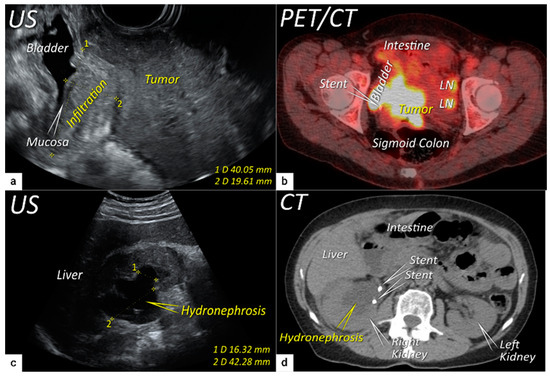

| T3 e | III e | Carcinoma involves the lower third of the vagina and/or extends to the pelvic side wall and/or causes hydronephrosis or non-functioning kidney | Tumour infiltration of the lower third of vagina or lateral pelvic side wall by US or MRI. Pelvic side wall infiltration is considered when the tumour causes hydroureter, infiltrates the obturator internus, piriformis, and levator ani muscles, encases the iliac vessels, or invades the pelvic bones on US or MRI. |

| T3b | IIIB | Tumour extension to the pelvic side wall and/or hydronephrosis or non-functioning kidney (unless known to be due to other cause). | US: Hypoechogenic tumour projections up to pelvic side wall +/− infiltration of iliac vessels, ureters, muscles, presence of hydronephrosis MRI: Hyperintense infiltration up to the pelvic side wall, loss of normal parametrial signal intensity and increased signal intensity in pelvic musculature due to tumour invasion seen on T2W-images. |

| T4 f | IVA f | Tumour invasion into the mucosa of the bladder or rectum (biopsy-proven) or into adjacent organs. | Tumour invasion into the mucosa of the bladder or rectum on imaging, confirmed by biopsy. US: Negative sliding sign, hypoechogenic tumour infiltration of bladder/rectal wall up to echogenic mucosa with polypoid tumour seen intraluminally. MRI: Focal or diffuse disruption of the normal T2-low signal intensity wall of the bladder/rectum, irregular or nodular wall, sometimes including an intraluminal tumour mass. Bulous edema sign, which is hyperintense thickening of the bladder mucosa on T2W images, is only an indirect sign of invasion and should not be regarded as T4 unless confirmed mucosal infiltration at cystoscopy. Infiltration of the posterior bladder wall without mucosal infiltration should not be regarded as T4a. |